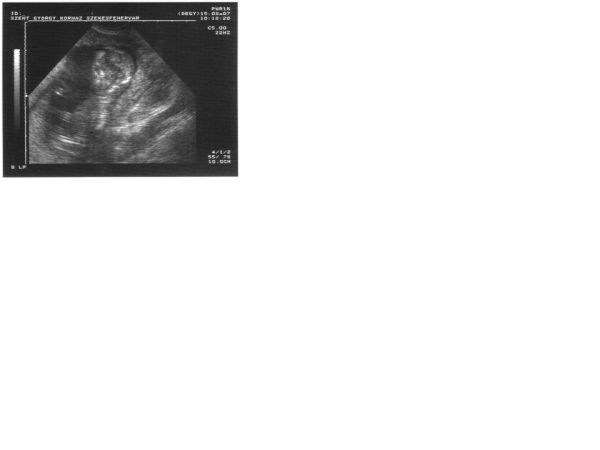

A 4d-s ultrahangra a Lotz Károly u.-ba, ahol te is voltál, mennyivel előtte kell bejelentkezni, mert szeretnék én is elmenni, és nem tudom milyen sokan járnak oda.